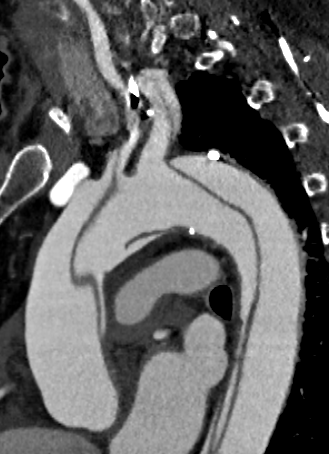

Fig.1., 2.: Hypertrophic obstructive cardiomyopathy: Longitudinal and short axis slices of delayed enhancement of contrast material in the heart: pathologic enhancement is visible in the myocardium in the asymmetrically thickened left ventricular wall, referring to a degenerative-fibrotic process.

In case of dilated cardiomyopathy, the enlargement occurs in the ventricles. The wall becomes thinner and the pump function becomes impaired, leading to the decrease of ejection fraction. Most commonly it is caused by coronary diseases, but metabolic diseases, inflammatory processes and toxic damage can also be a cause. The cardiac morphology and function are well assessable with echocardiography, while MRI can play a role in the differential diagnostics.